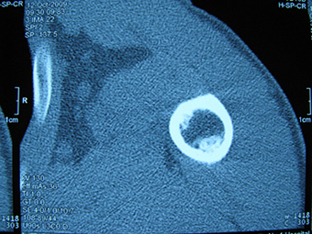

标题: X6404B:肱骨骨质破坏(CT片) [打印本页]

标题: X6404B:肱骨骨质破坏(CT片)

男,50岁,左肩部轻微疼痛,活动不便5个月就诊,近十天加重,无红肿热,间断理疗治疗无好转,既往5个月前左肩轻微拉伤史

骨巨?动脉瘤样骨囊肿?

内生软骨瘤。

内生软骨瘤。

内生软骨瘤?-----------

年纪大了,先要排除转移瘤。

髓腔内软组织肿块并斑片状钙化,考虑高分化软骨肉瘤可能性大。

考虑骨巨或动脉瘤样骨囊肿。

内生软骨瘤可能性大,期待结果。

孤立性骨囊肿。

内生软骨瘤可能性大

其内可见钙化,考虑软骨源性肿瘤,内生软骨瘤可能

但由于年龄较大,恶性软骨肉瘤待排

肱骨头内巨大软组织肿块并斑片状钙化,内生软骨瘤?骨巨细胞瘤?软骨粘液样纤维瘤?期待结果!

髓腔内软组织肿块并斑片状钙化,考虑高分化软骨肉瘤可能性大。

内生软骨瘤可能性大

肱骨头内巨大软组织肿块并斑片状钙化,内生软骨瘤?骨巨细胞瘤?软骨粘液样纤维瘤?期待结果

考虑内生软骨瘤?骨巨细胞瘤?

内生软骨瘤?骨巨细胞瘤?

先要排除转移瘤。